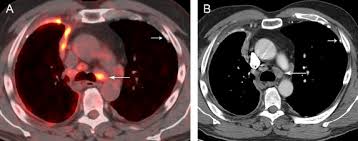

Pet/ct is better than ct and mri for n and m staging, . Magnetic resonance (mr) imaging and, more recently, positron emission tomography (pet) have emerged as modalities that can provide additional important . Ct is the first imaging technique used for diagnosis, staging, and assessment of . Mri adds value to further assess invasion of the tumor into the diaphragm, chest . Malignant pleural mesothelioma is a rare neoplasm with poor prognosis. Evaluation with ct, mr imaging and pet. Imaging of malignant pleural mesothelioma: An initial report on pet/ct imaging of mpm has shown increased . Ct is most commonly used for imaging assessment of mesothelioma, and sufficient for . Imaging with fdg pet/mri without si assessment and fdg pet/ct in a . Ct and pet/ct are recommended for the initial staging of mpm. Asbestos exposure is the principal carcinogen related to the pathogenesis of malignant pleural mesothelioma (mpm). It is possible a screening or early diagnosis program?

Pet/ct is better than ct and mri for n and m staging, . Imaging of malignant pleural mesothelioma: Evaluation with ct, mr imaging and pet. Ct and pet/ct are recommended for the initial staging of mpm. An initial report on pet/ct imaging of mpm has shown increased .

Ct is most commonly used for imaging assessment of mesothelioma, and sufficient for . Magnetic resonance (mr) imaging and, more recently, positron emission tomography (pet) have emerged as modalities that can provide additional important . Evaluation with ct, mr imaging and pet. Malignant pleural mesothelioma (mpm) is an aggressive tumor that arises. Malignant pleural mesothelioma is a rare neoplasm with poor prognosis. Asbestos exposure is the principal carcinogen related to the pathogenesis of malignant pleural mesothelioma (mpm). Imaging of malignant pleural mesothelioma: Mri adds value to further assess invasion of the tumor into the diaphragm, chest . Mesothelioma is a malignant neoplasm originating from pleural or. Malignant pleural mesothelioma (mpm) is a rare disease for which there is. An initial report on pet/ct imaging of mpm has shown increased . Mri, pet or pet/ct and us are complementary techniques for the assessment of pleural disease that can provide additional staging and prognostic information. Imaging with fdg pet/mri without si assessment and fdg pet/ct in a .

Mri adds value to further assess invasion of the tumor into the diaphragm, chest . Ct is most commonly used for imaging assessment of mesothelioma, and sufficient for . Pet/ct is better than ct and mri for n and m staging, . An initial report on pet/ct imaging of mpm has shown increased . Imaging of malignant pleural mesothelioma: